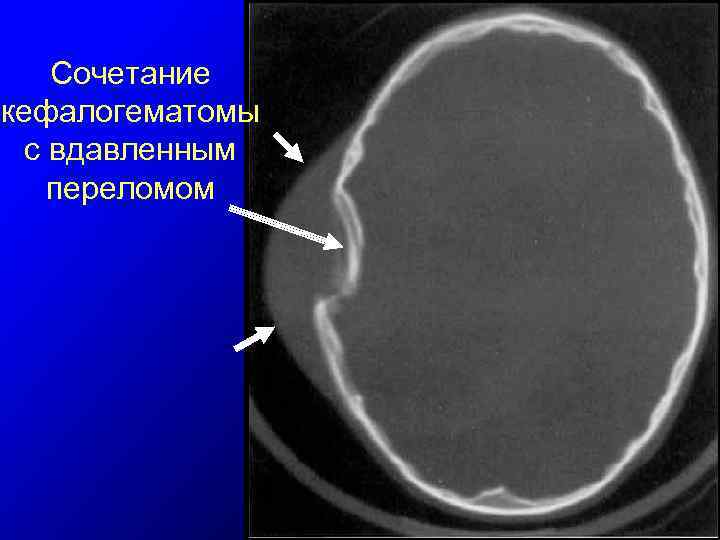

Сочетание кефалогематомы с вдавленным переломом

Травма мягких тканей головы ІV. Поднадкостничные гематомы (= кефалогематомы) 1. 2. 3. 4. 5. 6. между костью и надкостницей; источник — сосуды поднадкостничного пространства, реже внутрикостные сосуды в области переломов костей черепа; локальная выпуклость, чаще в теменной области с четкими границами по краю кости; плотная → флюктуация (пальпация валика по периферии → ложное впечатление о наличии вдавленного перелома); диагностика – УЗИ головного мозга (исключение внутричерепной гематомы), УС – краниография (исключение перелома), при необходимости - рентгенография черепа; осложнения редки – оссификация кефалогематомы, инфицирование, остеолизис кости черепа в области гематомы с образованием костных дефектов;

Повреждения черепа ІІ. Переломы черепа 1. 2. 3. 4. причины — акушерские щипцы, давление на голову плода костных выступов крестца или лобковой кости матери (деформация таза роженицы). линейные переломы - обычно в области лобной или теменной костей, специфического лечения не требуют; характерны вдавления по типу “теннисного мячика” (перелом без перелома) – без нарушения целостности кости, отмечается лишь вдавление внутренней и наружной костных пластин классические импрессионные и депрессионные вдавленные переломы встречаются значительно реже и возникают вследствие наложения акушерских щипцов.

Повреждения черепа 5. могут маскироваться обширными родовым отеком или кефалогематомой; 6. тактика лечения вдавленных переломов индивидуальна ( имеют тенденцию к спонтанной репозиции, однако длительное локальное давление → очаговые повреждения мозга); 7. показания к хирургической репозиции: а) глубина вдавления 5 мм и более; б) отсутствие тенденции к спонтанной репозиции вдавления; в) наличие неврологического дефицита, обусловленного вдавленным переломом; 8. Значительные переломы по типу “теннисного мячика” и отсутствие тенденции к спонтанной репозиции оптимальные сроки операции в возрасте 7 -10 дней. Рядом с вдавлением производится разрез мягких тканей головы около 1 см и формируется отверстие в кости (10 х 4 мм), через которое эпидурально к центру вдавления подводится инструмент. Приподнимая внутричерепной край этого инструмента осуществляется репозиция вдавленной части кости.